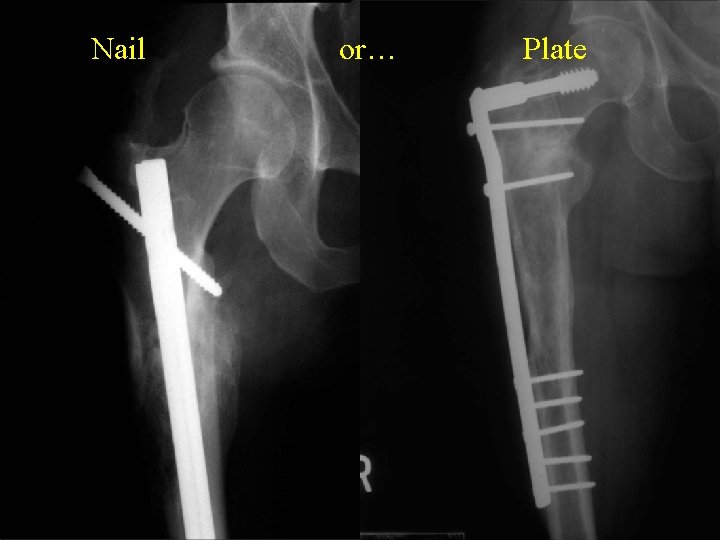

Nail or… Plate